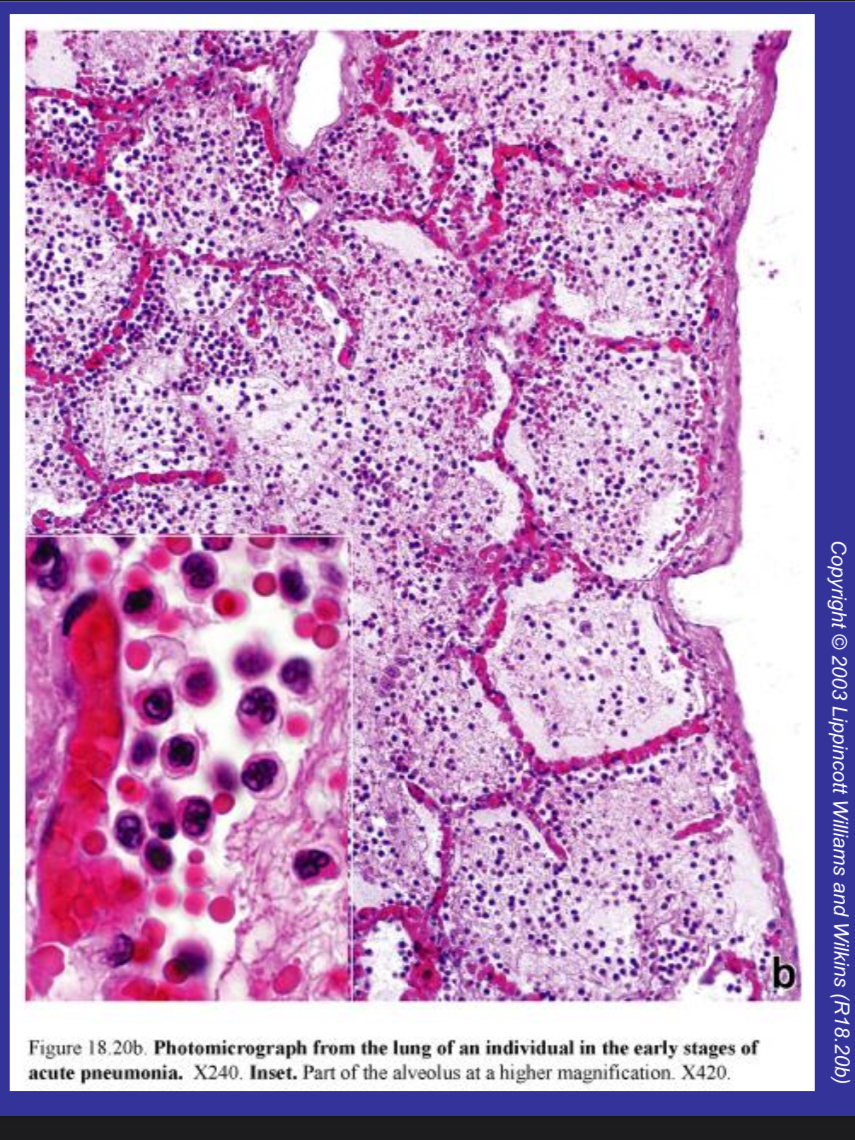

Pneumonia

Inflammation of the lung caused by bacteria. The lung consolidates as the alveoli fill with inflammatory cells. • Most common organism is Streptococcus pneumoniae. • Others are: Haemophilus influenzae Staphylococcus aureus Legionella pneumophila and Mycoplasma pneumoniae